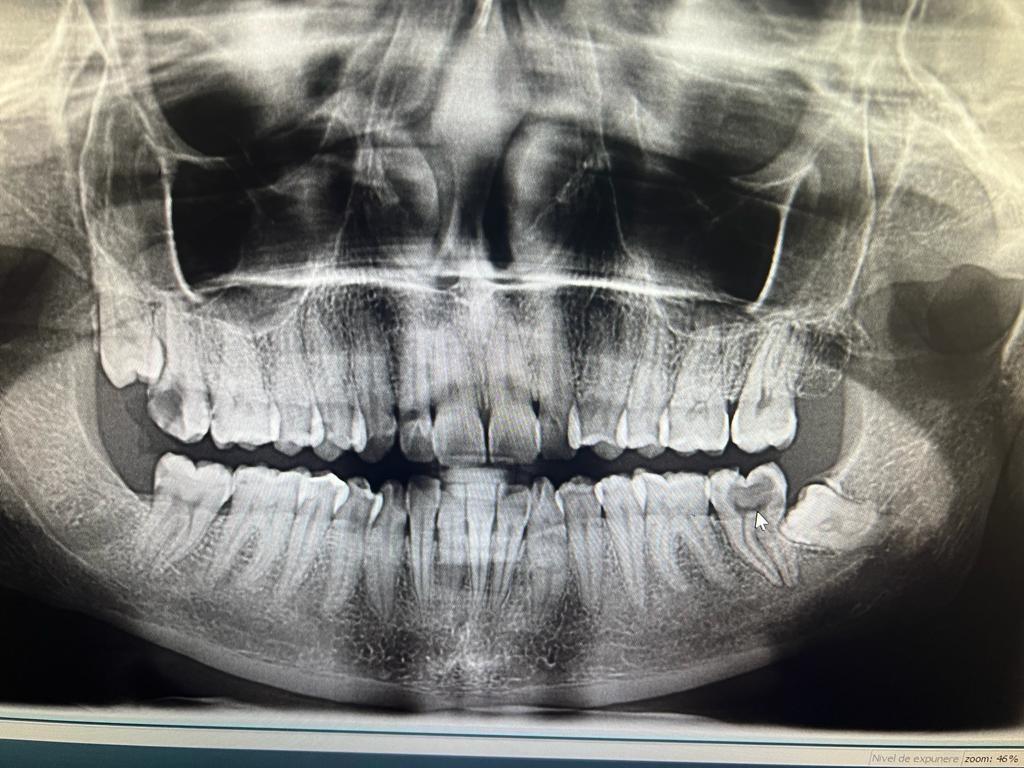

Clinica LUY ESTHETIC ART defineste parodontoza ca fiind rezultatul direct al placii dentare, care se depune pe suprafata dintilor, dar si in apropiere de marginea gingivala. Aceasta boala duce la pierderea dintilor, chiar daca ei sunt aparent sanatosi si nu prezinta carii. Edentatiile, afecteaza vorbirea, aspectul, dar si capacitatea de a mesteca.

Boala parodontala are un caracter progresiv. Pentru cazurile mai grave, recomandam tratamentul parodontal chirurgical rezectiv sau regenerativ.

O igiena bucala necorespunzatoare, fumatul, placa bacteriana si alte boli generale, permit bacteriilor sa se dezvolte in cavitatea bucala.

Recomandam controale periodice (3-6 luni) pentru igienizari profesionale: detartraj, periaj dentar, air-flow etc. Aceste operatiuni asigura sanatatea gingiei, iar osul alveolar si ligamentele parodontale isi pastreaza integritatea.